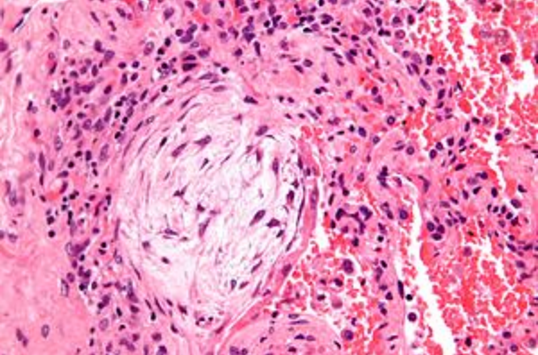

_____ bodies are seen in cryptogenic organizing pneumonia.